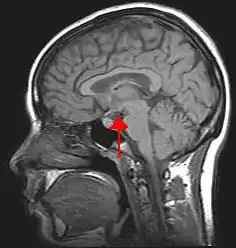

Since the nervous system does not store nutrients, it must receive a continuous supply from blood. Any interruption to the flow of blood may bring brain damage or death. The nervous system maintains homeostasis by controlling and regulating the other parts of the body. A deviation from a normal set point acts as a stimulus to a receptor, which sends nerve impulses to a regulating center in the brain. The brain directs an effector to act in such a way that an adaptive response takes place. If, for example, the deviation was a lowering of body temperature, the effector acts to increase body temperature. The adaptive response returns the body to a state of normalcy and the receptor, the regulating center, and the effector temporarily cease their activities. Since the effector is regulated by the very conditions it produced, this process is called control by negative feedback. This manner of regulating normalcy results in a fluctuation between two extreme levels. Not until body temperature drops below normal do receptors stimulate the regulating center and effectors act to raise body temperature. Regulating centers are located in the central nervous system, consisting of the brain and spinal cord. The hypothalamus is a portion of the brain particularly concerned with homeostasis; it influences the action of the medulla oblongata, a lower part of the brain, the autonomic nervous system, and the pituitary gland.